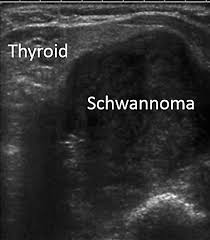

頚部神経鞘腫(schwannoma)は硬く、血流に乏しい腫瘤で、発生母体の神経(写真では迷走神経)に連続しています。

- 充実性、均一エコー型(solid pattern);エラストグラフィーでは硬い

- 不均一エコー型(multiple microcystic pattern)

- 辺縁増強を伴う嚢胞型(cystic pattern)

があります(耳鼻34:677 ~683 ,1988.)。